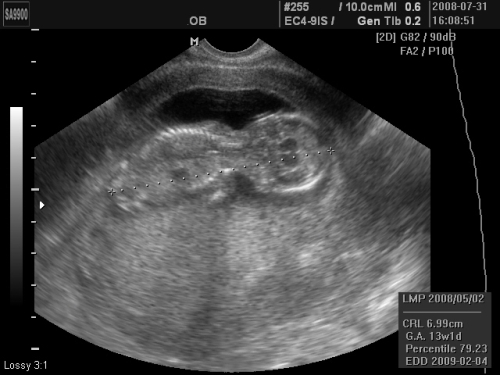

Hát túl vagyunk a nyaki redő mérésen, fantasztikus élmény volt, és ami a legfontosabb, minden rendben van. A törpe CRL-je 6,57 cm és a nyaki redő 1,1 mm. Azt mondta a doki, hogy 12+5 napos, azaz ma már 12+6 eszerint, úgyhogy van egy újabb dátumom a várható születési időpontra

Mi az Istenhegyi Géndiagnosztikai-ban voltunk, és nagyon meg voltam elégedve velük, az ember csak ámul, hogy ma már micsoda technikák vannak ... Egy hatalmas tévén nézhettem, ahogy produkálja magát a drágaság, és mivel elég nehezen akart abba a pozícióba fordulni, hogy a doki meg tudja mérni, így kb. 10 percig gyönyörködhettünk benne. A doki nagyon jó fej volt, közben kommentálta a dolgokat